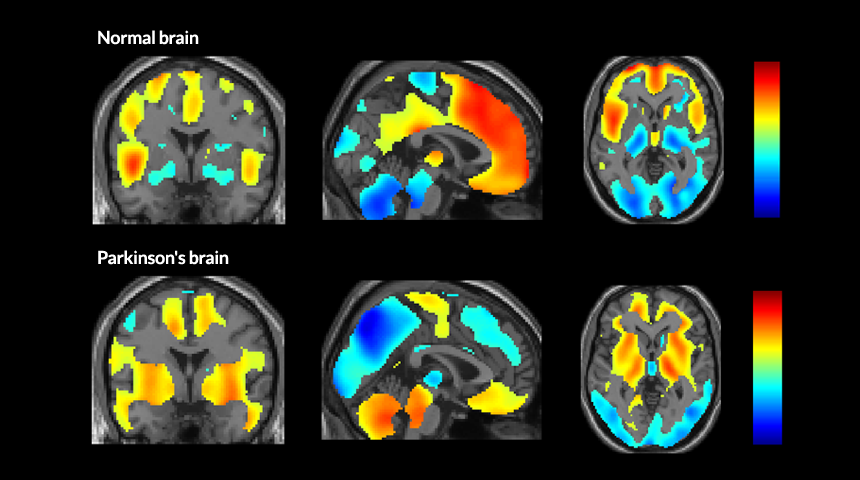

NETWORKING  Brain scans reveal the part of the brain that’s active (red shows most activity; blue shows least) when people are not thinking about anything in particular. In healthy people (top row), these coordinated areas of the brain are called the default mode network. But in people with mild to moderate Parkinson’s disease (bottom row), a new, abnormal network takes over.

P. Spetsieris et al/ PNAS 2015, adapted by S. Egts

Networks of brain regions that are active when the brain is at rest — not thinking about anything in particular — differ between healthy people and those with Parkinson’s or Alzheimer’s diseases, a new study finds.